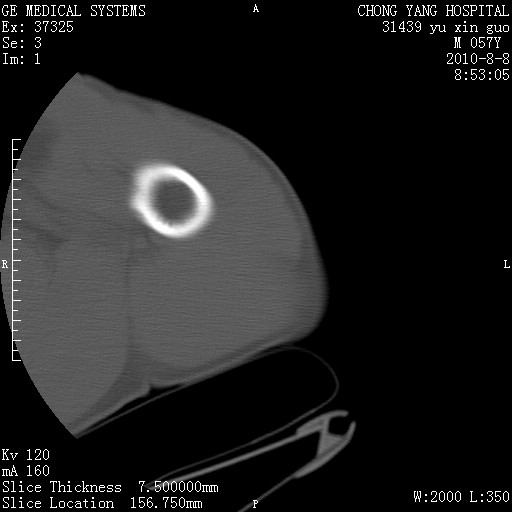

标题: CT28267:M57Y 上臂包块8年余。 [打印本页]

标题: CT28267:M57Y 上臂包块8年余。

包膜光滑、完整的脂肪密度肿块,支持脂肪瘤。